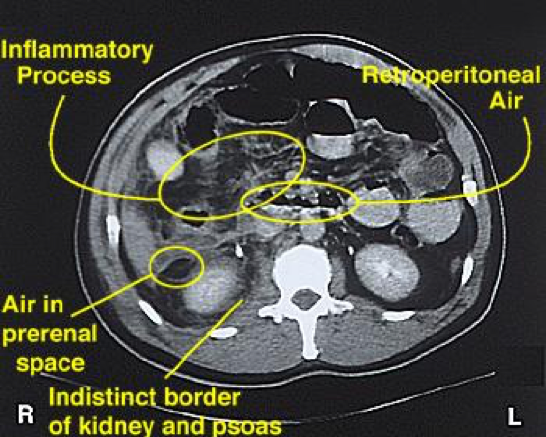

- Abdominal CT

- Much more sensitive and can also identify the specific causes

- Can also identify a transition point

- Other radiological signs on CT consistent with SBO include:

- Bowel wall thickening > 3mm

- Submucosal edema

- Mesenteric edema

- Ascites

- Target sign (intussusception)

- Whirl sign (volvulus)

- Venous cut-off sign (thrombosis)